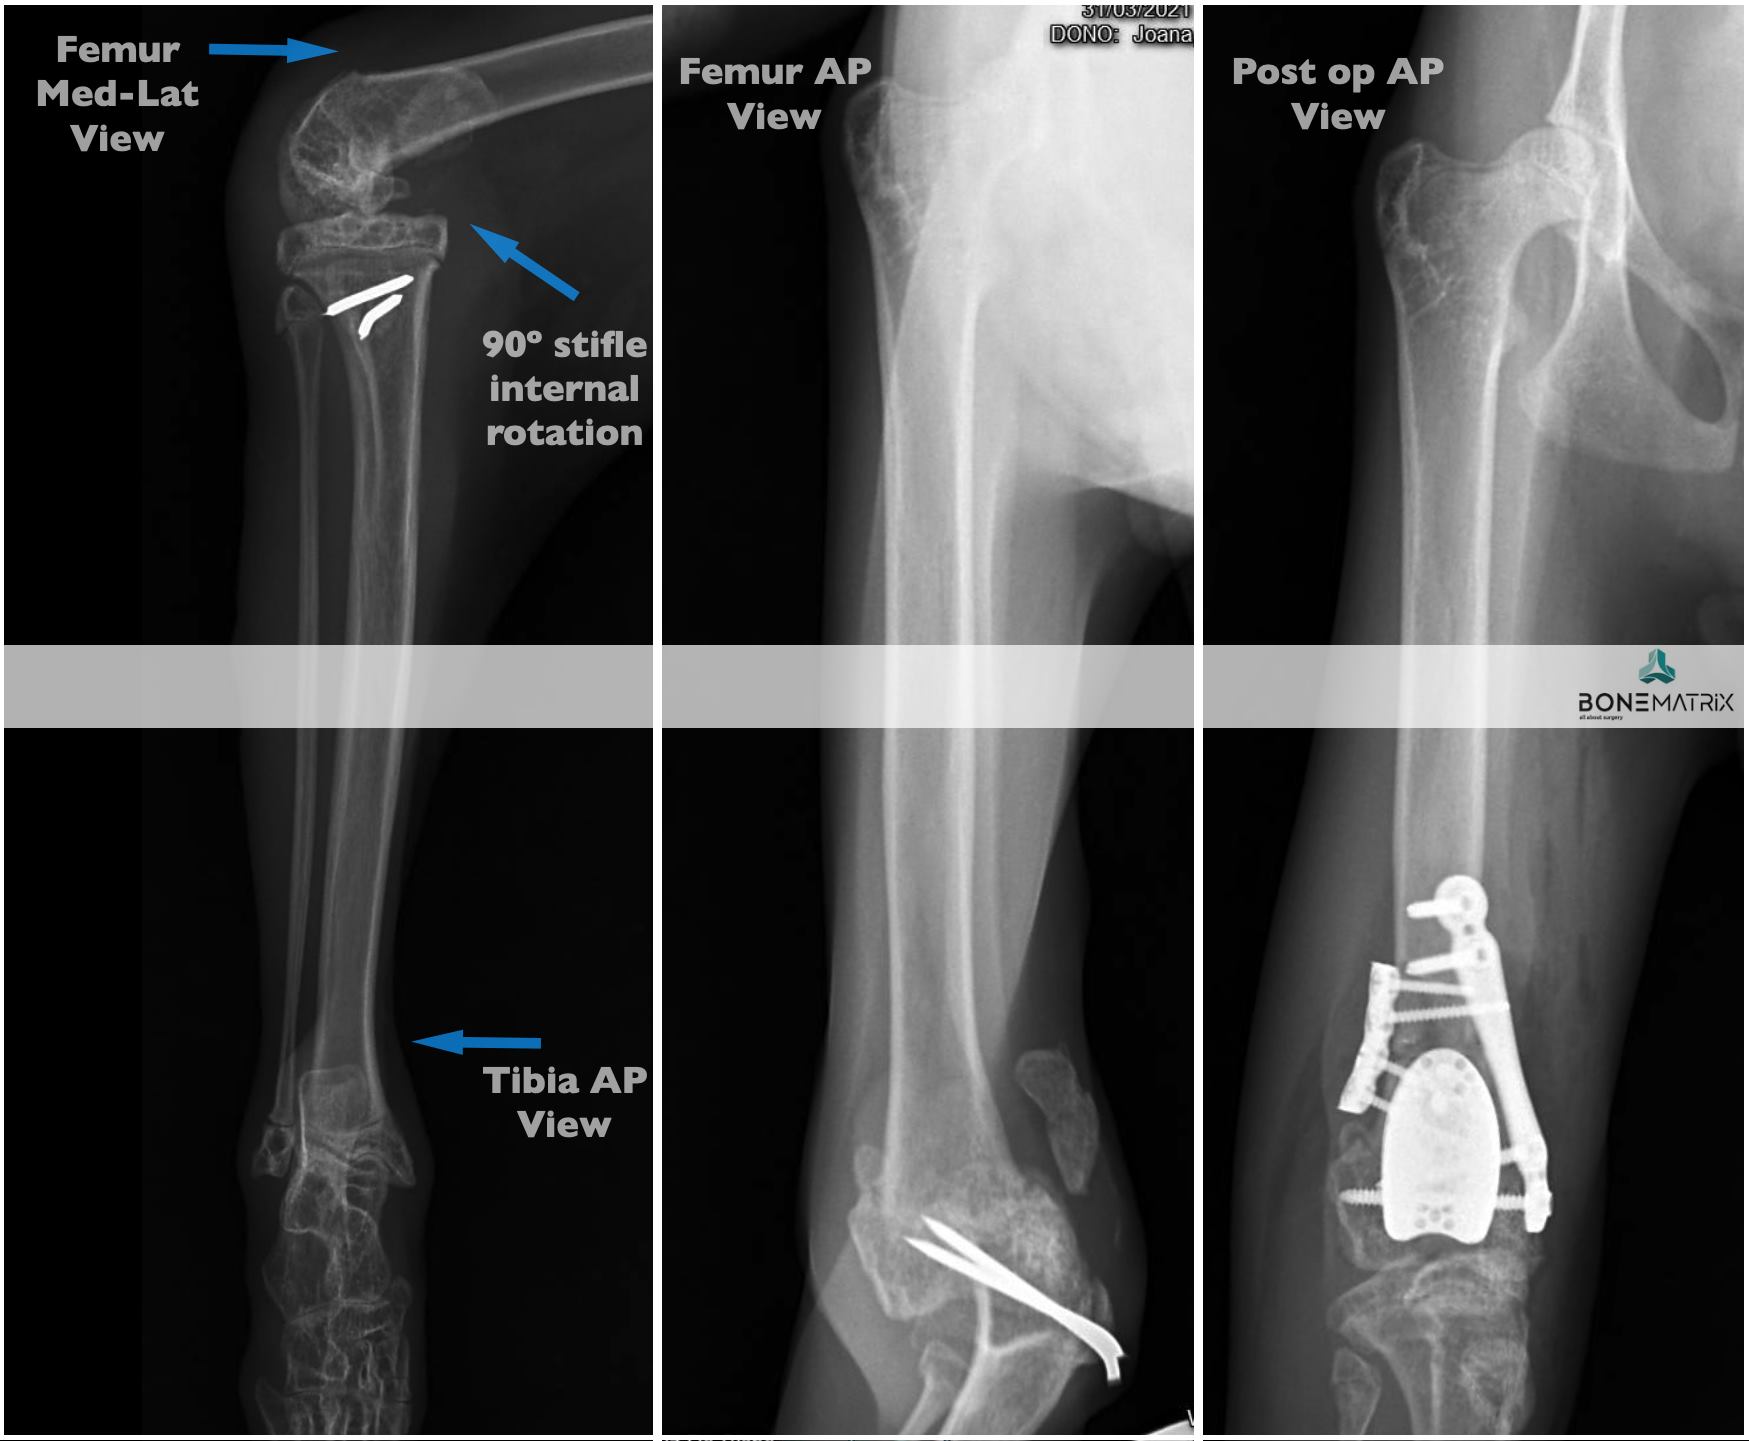

Romeu - deformidade angular iatrogénica

Porque não devemos colocar talas em animais em crescimento